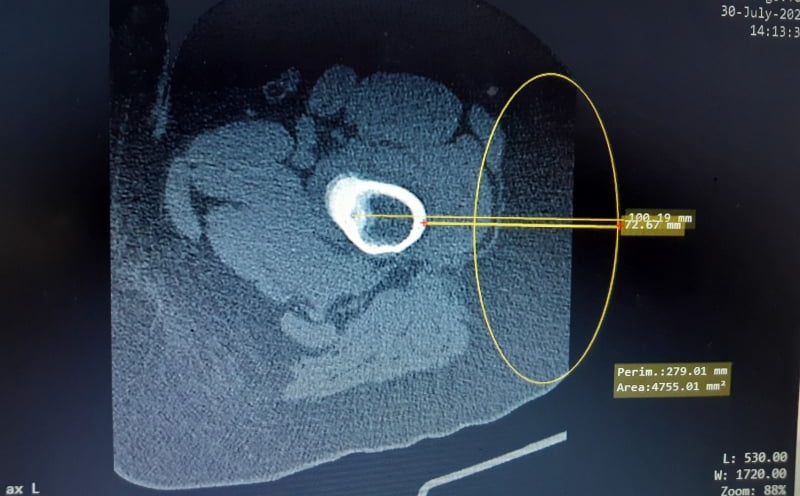

Дете с диагноза остеоид остеома, доброкачествен тумор на костите беше излекувано с радиочестотна аблация на нидуса под скенер контрол.

Симптоматиката при пациенти с подобно заболяване се изразява в силна, нетърпима болка в определена част от тялото, с пристъпен нощен характер в зоната където се намира и туморното образование. В случаят оплакванията на детето са в областта на лявото бедро. Образуванието се намира вътре в костта на момчето.

Екип от анестезиолог-реаниматор, рентгенолог и д-р Сергей Стоянов ортопед-травматолог провежда радиочестотната аблация, с която елиминира всички недостатъци на иначе известната конвенционална хирургическа намеса. Методът се провежда като под скенер контрол с тънка игла се стига до ядрото на тумора, и се нагрява за определен период от време при опеределена температура, което е достатъчно за да отстрани образуванието, тъй като неговата структура е белтъчна и то загива. По този начин пациентът е напълно излекуван и се прекратява цялата симптоматика на заболяването.

„Въведох лечението с радиочестотна аблация на нидуса под скенер контрол, тъй като при него разчитаме на топлина. Вдигаме локално температурата до 90 градуса като имаме контрол на полето, то е много малко един квадратен см което напълно отговаря на най-големия възможен размер на остеоид остеома). Нагрява се само локално, там където е самият тумор . Първо си верифицираме, че сме попаднали в туморното ядро под скенер контрол и след това загряваме ядрото на образуванието.“, разказва д-р Стоянов.